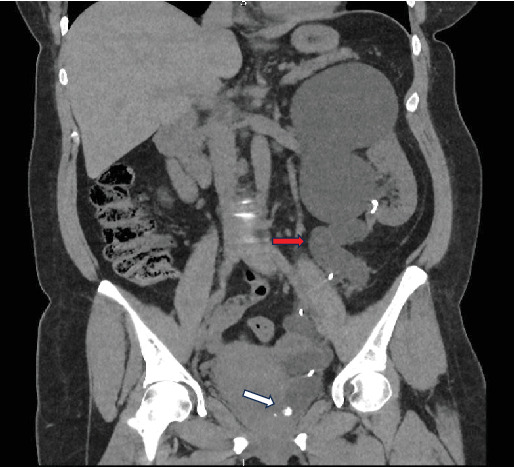

Duplex renal collecting system is a relatively common congenital abnormality affecting equally both pelvicalyceal systems. Although usually it is an incidental finding, it can cause significant problems to the patients such as recurrent urinary tract infections, hydronephrosis, and lithiasis. In this study, we describe an interesting surgical management option for a patient with upper moiety hydronephrosis and lithiasis of the aberrant ureter, achieving resolution of the hydronephrosis and complete removal of the calculus. A 49-year-old female patient presented with symptoms of left colicky pain. During the initial investigation, a left-sided duplex renal collecting system with severely hydronephrotic upper pole moiety and grossly dilated tortuous ureter with distal calculus and ectopic insertion to urinary bladder was identified. On cystoscopy, the upper moiety ureteric opening was identified distally to the urethral sphincter. Under ultrasound guidance, endoscopic transvesical resection was performed distal to the stented lower moiety ureteric orifice, resulting in the identification of the stone and extraction. Short- and long-term follow-up demonstrated no recurrence of the stone and significant resolution of the hydronephrosis. In conclusion, in this case report, we describe an unusual anatomical variation of the upper moiety outflow, and we introduce a new technique of intravesical ultrasound-guided removal of an obstructive calculus.